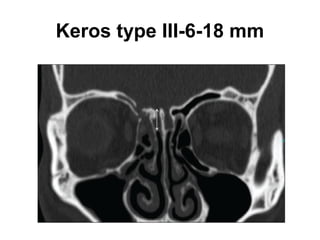

Olfactory fossa

• The depth of the olfactory fossa is determined by

the height of the lateral lamella of the cribriform

plate, which is part of the ethmoid bone. In 1962,

Keros had classified the depth of the olfactory

fossa into three types, that is,

• Keros type I: <3 mm,

• type II: 4-7 mm , and

• type III: 8-16 mm.-Kero type III is most

vulnerable to iatrogenic injury.

Keros type I-< 3 mm

Keros type II- 4 to 7 mm

Keros type III-6-18 mm

Olfactory fossa • Thedepth of the olfactory fossa is determined by the height of the lateral lamella of the cribriform plate, which is part of the ethmoid bone. In 1962, Keros had classified the depth of the olfactory fossa into three types, that is, • Keros type I: <3 mm, • type II: 4-7 mm , and • type III: 8-16 mm.-Kero type III is most vulnerable to iatrogenic injury.